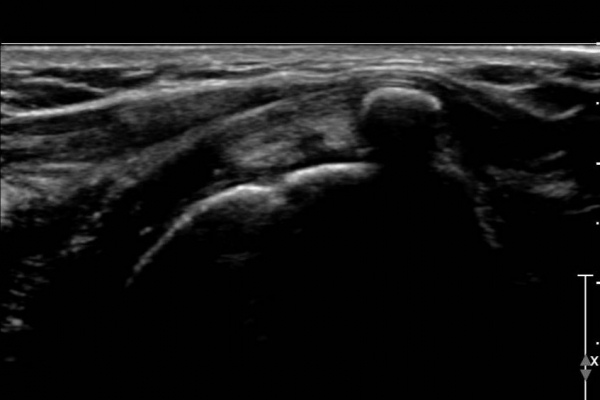

ÃÊÀ½ÆÄ °Ë»ç :  ¿À±¸µ¹±â °ßºÀÀδë Á¾´Ü¸é°Ë»ç¿¡¼­ ÀÎ´ë ½ÉÃþ¿¡ ¼ö¾×Àú·ù°¡ °üÂûµÇ´Âµ¥(»çÁø 1) ÀÌ °ÍÀº

¸¸¼ºÀûÀÎ Ãæµ¹ÁõÈıºÀ» ¾Ï½ÃÇÑ´Ù.